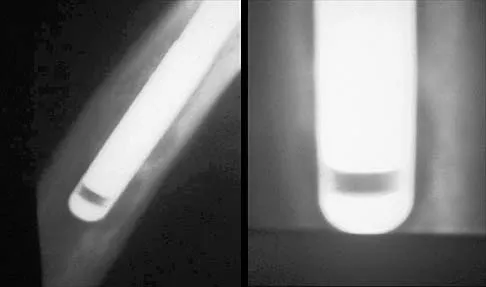

What is the most appropriate treatment for a 50-year-old woman who sustains the injury shown in Figures 14a and 14b?

This intra-articular distal humerus fracture with displacement at the joint surface is best treated with surgical fixation. The most biomechanically sound construct is two plates applied to either column 180 degrees from one another. Elbow arthroplasty is most appropriate for low demand elderly patients. Schemitsch EH, Tencer AF, Henley MB: Biomechanical evaluation of methods of internal fixation of the distal humerus. J Orthop Trauma 1994;8:468-475. McCarty LP, Ring D, Jupiter JB: Management of distal humerus fractures. Am J Orthop 2005;34:430-438.